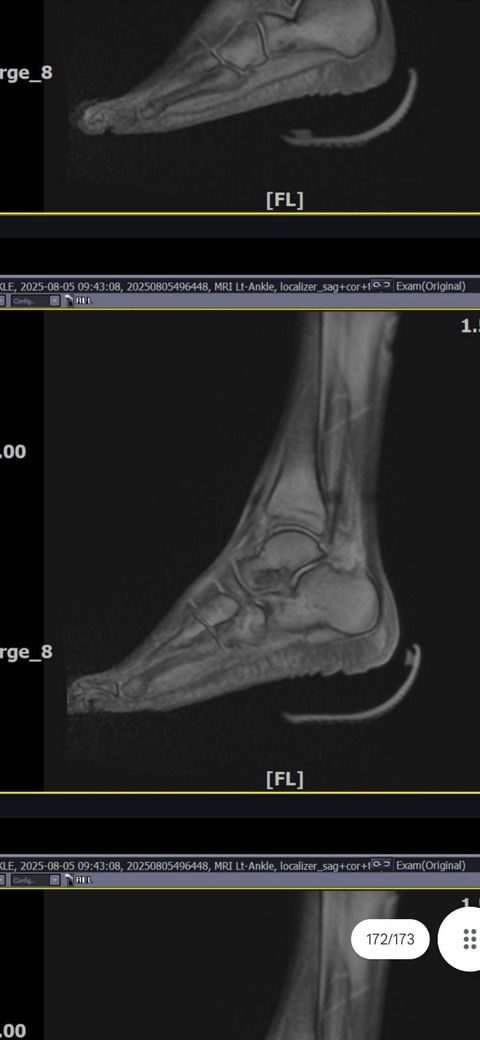

발목인대 상태 질문드립니다. (mri사진 첨부)

그래도 통증이 남아 8월 5일에 MRI를 촬영했는데, 병원에서는 “인대는 이어져 있고, 이 정도면 재활운동으로 호전될 것”이라는 설명을 들었습니다.

MRI 상 전거비인대와 발목 상태가 정말 회복 단계인지, 아니면 만성으로 넘어가는 건 아닌지 전문가분들의

의견을 듣고 싶습니다.

그리고, 처음 초음파 사진(6월 촬영)과 비교하여

mri 사진(8월 촬영)상 인대가 호전됬는지도

알고 싶습니다.

올려주신 mri를 보면 전거비인대는 연속성이 유지되고 있고 파열이나 큰 손상 흔적은 없어 재활로 회복 가능한 상태로 보입니다 다만 3개월 가까이 활동 시 통증과 미열감이 남아 있는 것은 조직 회복이 아직 완전히 끝나지 않았거나 주변 연부조직 관절 움직임 제한 등으로 인한 과민 반응일 수 있습니다.

초음파와 비교하면 mri 상으로 인대 연속성이 확인되므로 심각한 악화나 재파열은 아닌 것으로 판단됩니다